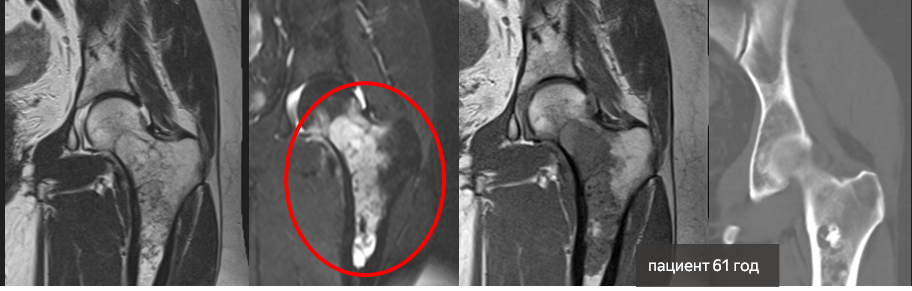

Второй редкий случай у пациентки 61 года. С жалобами на боли в тазобедренном суставе женщина обратилась к травматологу-ортопеду. Дополнительным обследованием была выполнена компьютерная томография.

В проксимальном отделе бедренной кости выявлено объемное образование более 10 сантиметров неоднородной структуры с множеством кальцинатов.

Предположительно, у пациентки хондросаркома. Для уточнения диагноза женщина направлена к онкологам.